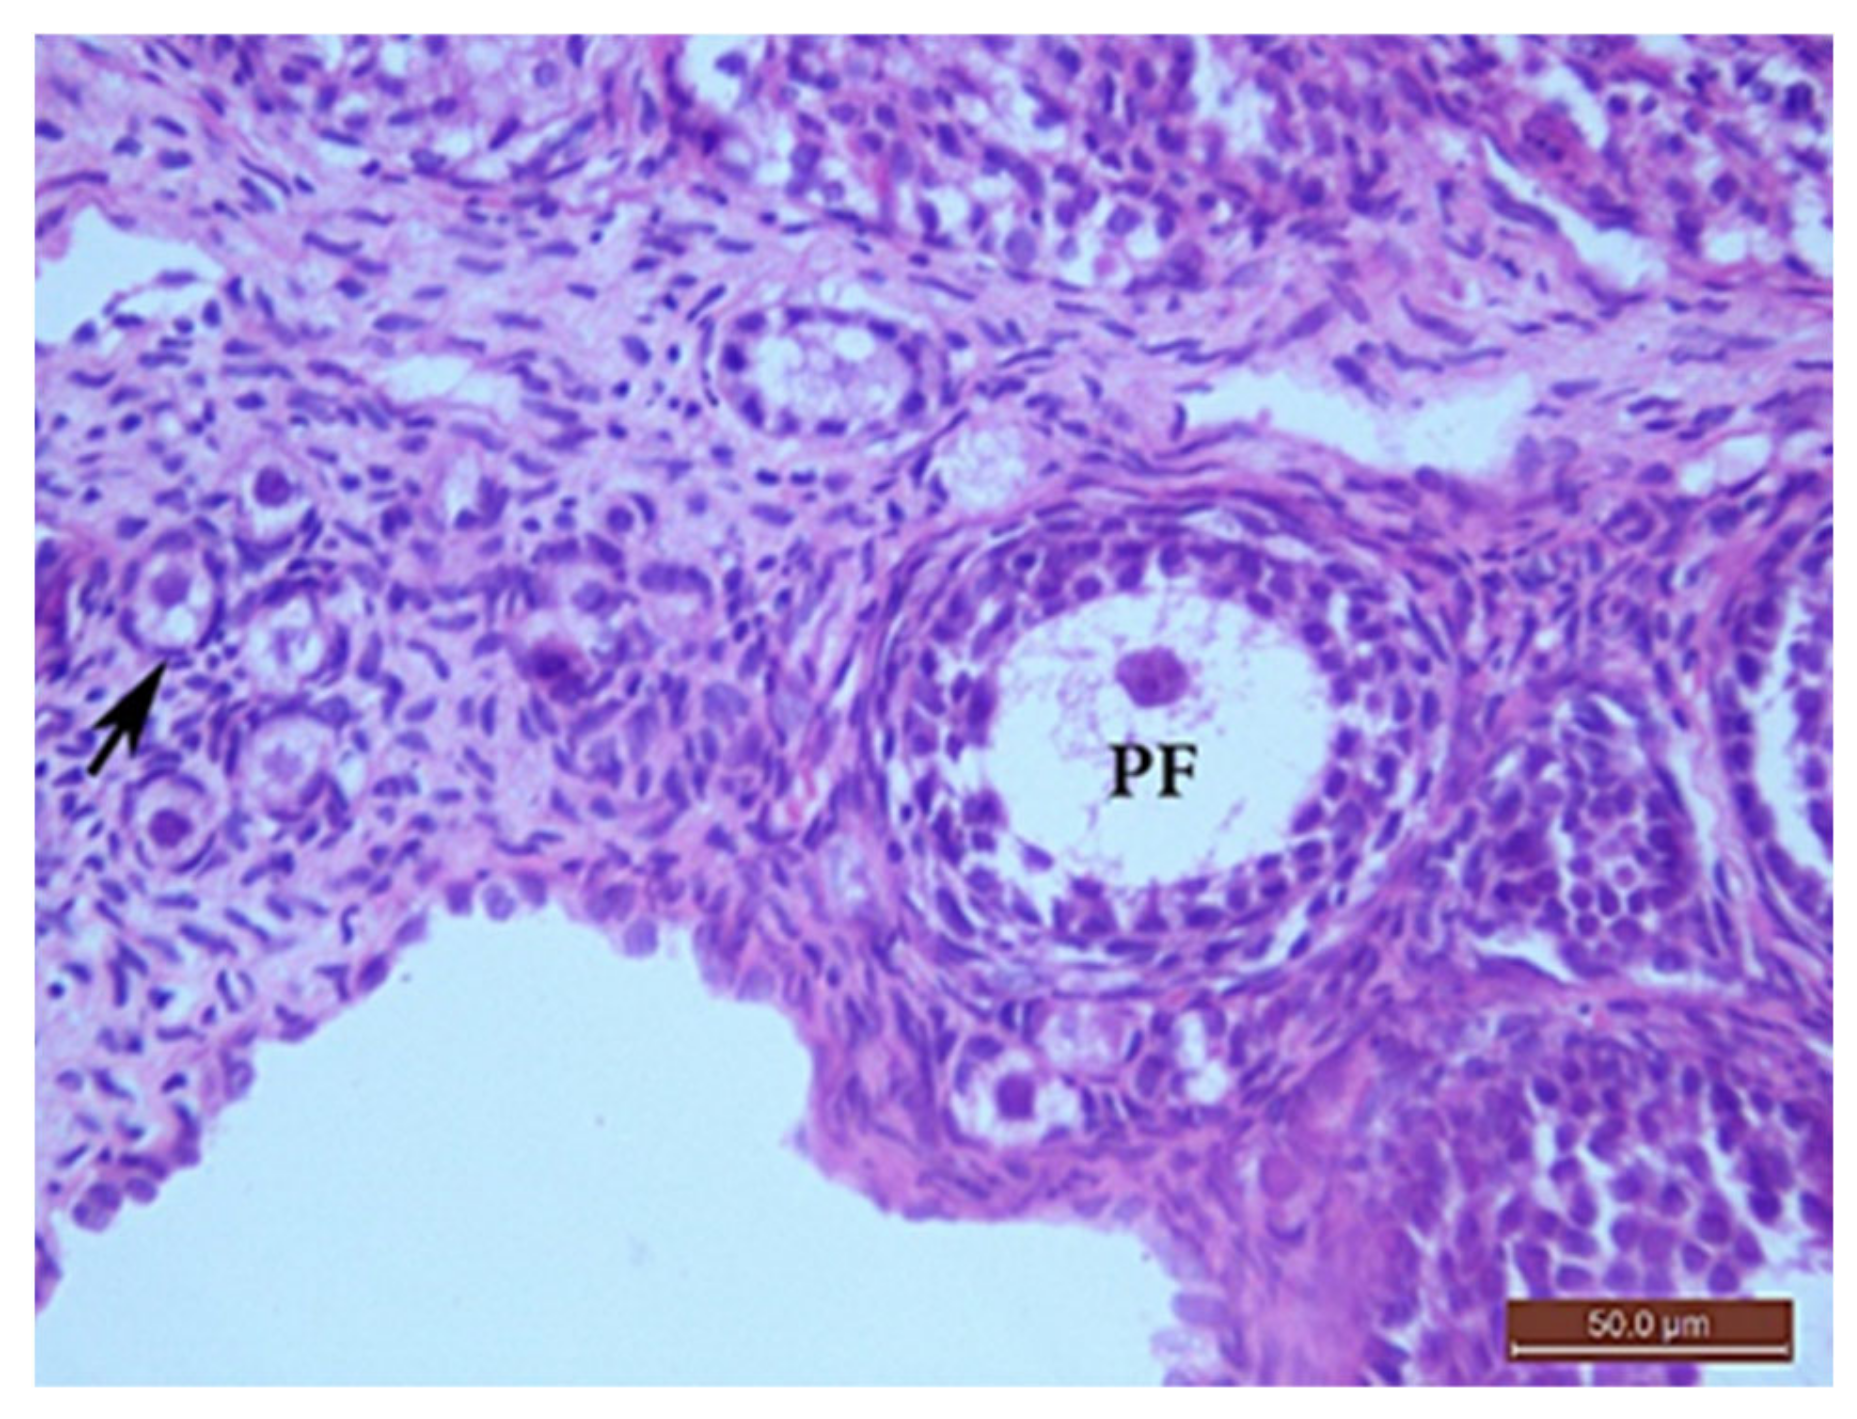

The Control Group (Group I, Figure 1, Figure 2, Figure 3 and Figure 4)